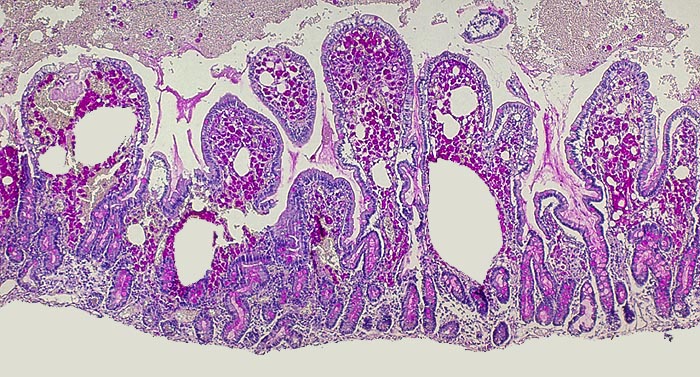

AP/ Morbus Whipple

Morbus Whipple

Dünndarm